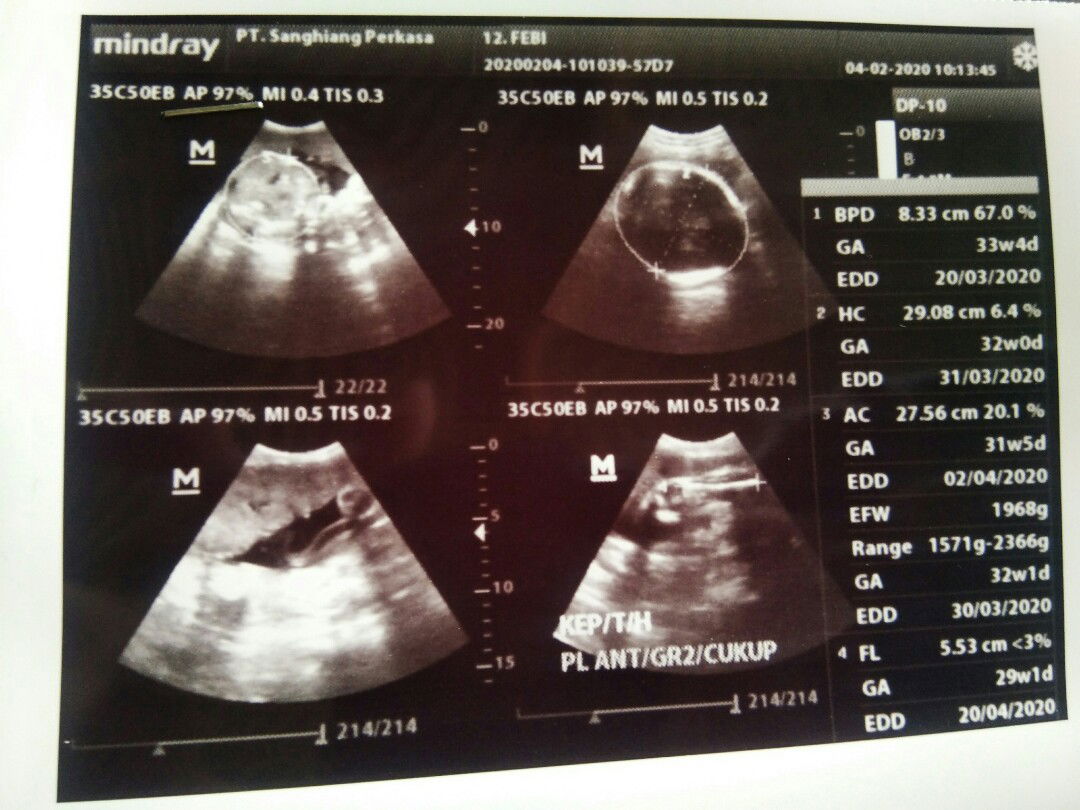

Apakah hasil USG selalu akurat?

Bun sharing dong pengalaman hasil usg tidak selalu sama dengan realita.. Sy kemaren usg uk 32w FL (panjang tulang paha janin) 5,53cm